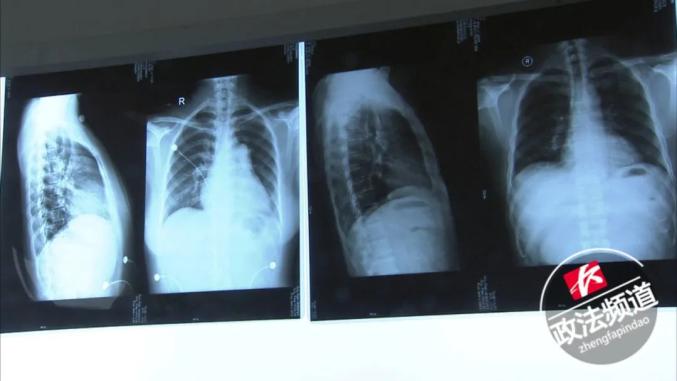

中南大学湘雅二医院心血管内科主治医师罗俊表示:“CT显示这个病人的心脏明显增大,比我们正常人的心脏大了至少是有三倍,而且是一个不正常的增大。”